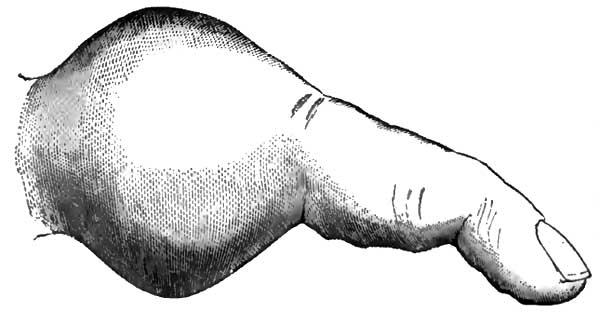

| 6. | PEMPHIGUS BULLA FROM A NEW-BORN SYPHILITIC CHILD |

| 10. | THE SAME AS FIG. 9 |

| 11. | SERRATIONS OF NORMAL INCISOR TEETH |